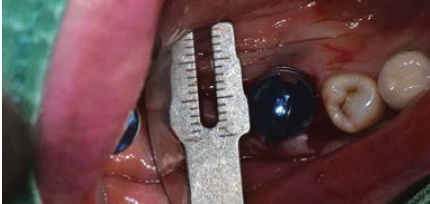

Multiple implants & bridge

Volume Up Gauge로 직경 확인 (Ø8.5)

-

Volume Up Gauge홈에 맞춰 Point Drill 위치

Point Drill 후 생성된 구멍에 Ø8.5 Volume Up Parallel Pin을 끼움

이 후, 앞의 임플란트 위치에 맞춰 Volume Up Gauge 위치 시켜 직경확인 (Ø7.5)

Volume Up Gauge 홈에 맞춰 Point Drill 위치

Point Drill 후 생성된 구멍에 Ø7.5 Volume Up Parallel Pin을 끼움

제조사의 식립 순서에 맞춰 Drilling 후 Fixture 식립

Fixture에 Volume Up Healing Abutment 체결

Easy Seal 등과 같은 수복재로 Screw Hole을 충전